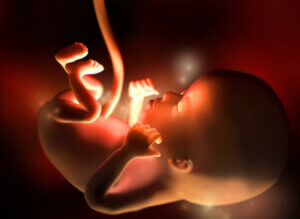

12. raskausviikko on ensimmäisen raskauskolmanneksen viimeinen viikko. Noin 4-5 sentin pituisen ja 5-10 gramman painoisen sikiön sydän sykkii jo voimakkaasti, noin 160 lyöntiä minuutissa. Nyt noin luumun tai passionhedelmän kokoinen sikiö kasvaa 11. ja 12. raskausviikon aikana 15 %.

Tässä vaiheessa raskautta sikiön liikkeet alkavat lisääntyä, vaikka odottava äiti ei niitä vielä tunnekaan. Sikiön raajat ovat jo muodostuneet ja sisäelimet alkavat kehittyä nopeasti. Suolisto, joka on tähän asti ollut yhteydessä napanuoraan, on nyt siirtynyt vatsaonteloon. Sikiön pää alkaa muotoutua pyöreämmäksi ja korvat siirtyä lopullisille paikoilleen. Sikiö pystyy jo avaamaan ja sulkemaan suunsa, haukottelemaan, nielemään ja nikottelemaan. Sen kynnet ja äänihuulet alkavat muodostua. 12. raskausviikon aikana sikiön munuaiset alkavat tuottaa pieniä määriä virtsaa, ja myös ensimmäisiä ihokarvoja alkaa ilmaantua.